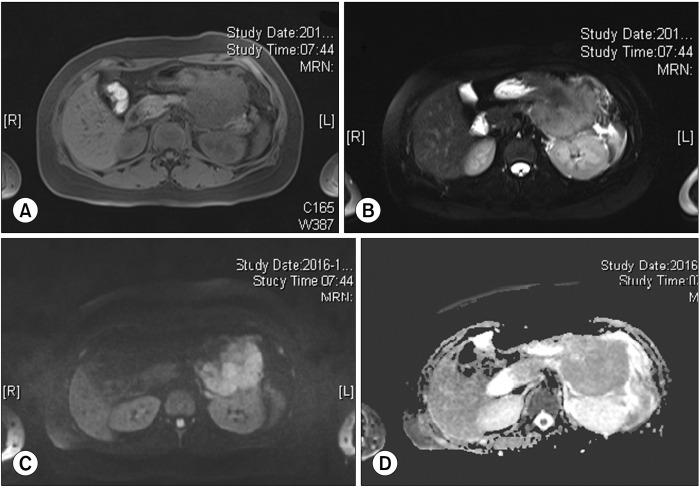

A 23-year-old Korean female presented epigastric pain of two-months' duration. She had a laparoscopic ovarian cyst excision 8 months previously. Clinical examination was normal. An abdominal computed tomogram (CT) demonstrated a 10-cm solid mass in the distal pancreas, with signs of splenic artery and vein occlusion, gastric and transverse colon invasion. Operative findings showed a mass involving distal pancreas, invasive to the posterior wall of the antrum of the stomach and transverse colon and 4th portion of the duodenum without lymph node involvement. The surgery consisted of a distal pancreatectomy, splenectomy and combined partial resection of the stomach, transverse colon and 4th portion of the duodenum. The immunohistochemistry and histopathological features were consistent with a confirmed diagnosis of intra-abdominal desmoid type fibromatosis (DTF). The prognosis of pancreatic DTF is not known and she showed no recurrence or distant metastasis during a 3 year follow-up. Herein we report a rare case with an isolated, sporadic, and non-trauma-related DTF, located at the pancreatic body and tail.

一名23岁的韩国女性出现了持续两个月的上腹部疼痛。她在8个月前接受了腹腔镜卵巢囊肿切除术。临床检查正常。腹部计算机断层扫描(CT)显示胰腺远端有一个10厘米的实性肿块,伴有脾动静脉闭塞、胃和横结肠受侵的迹象。手术所见显示肿块累及胰腺远端,侵犯胃窦后壁、横结肠和十二指肠第四部,无淋巴结受累。手术包括远端胰腺切除术、脾切除术以及胃、横结肠和十二指肠第四部的联合部分切除术。免疫组化和组织病理学特征与确诊的腹腔内硬纤维瘤病(DTF)一致。胰腺DTF的预后尚不清楚,在3年的随访中她未出现复发或远处转移。在此我们报告一例罕见的孤立、散发性且与创伤无关的DTF病例,位于胰体尾部。